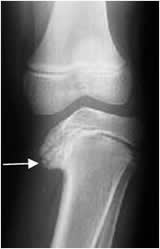

Fig 66. Angulo femorotibial.

Rx AP. Medición del ángulo entre los ejes del fémur y la tibia.

Fig 67. Angulo femorotibial.

Rx AP. Medición del ángulo entre los ejes del fémur y la tibia, el cual tiene normalmente vértice medial.

El niño desde el nacimiento hasta los 24 y 30 meses, puede presentar un genu varo fisiológico. (Fig 68). Este debe ser bilateral y con una distancia menor de 6 cm, entre los cóndilos femorales. El ángulo del eje femorotibial no debe ser mayor de 28º y no requiere de tratamiento. Si el genu varo persiste después de los 36 meses, se debe diferenciar del raquitismo, la enfermedad de Blount (Retardo en el crecimiento posteromedial de la tibia, la cual es mas corta), malformación congénita, infección, trauma, osteoartrosis, etc. (1). (Fig 69 y 70).

Se considera patológico un ángulo femorotibial mayor de 177º y cualquier genu varo unilateral. (1).